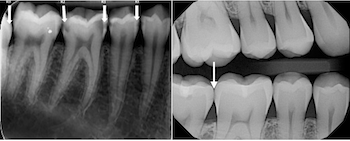

Dental x-rays help your dentist see underlying issue not obvious to the naked eye. The arrows show dental decay and the areas most commonly affected by dental decay. Do you really need dental X-rays? Yes, absolutely. Dental X-rays are a screening procedure that allows the dentist to get “the full picture” and to understand what […]